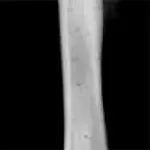

A radiograph displays a long bone with visible cortical bone structure and several small lucent areas indicating potential lesions or abnormalities. The image is set against a dark background, highlighting the bone's outline and any irregularities.

Figure 3D. Several small holes were drilled in the affected cortex (osteostixis) to encourage neovascularization and bone healing. The lameness resolved after treatment.